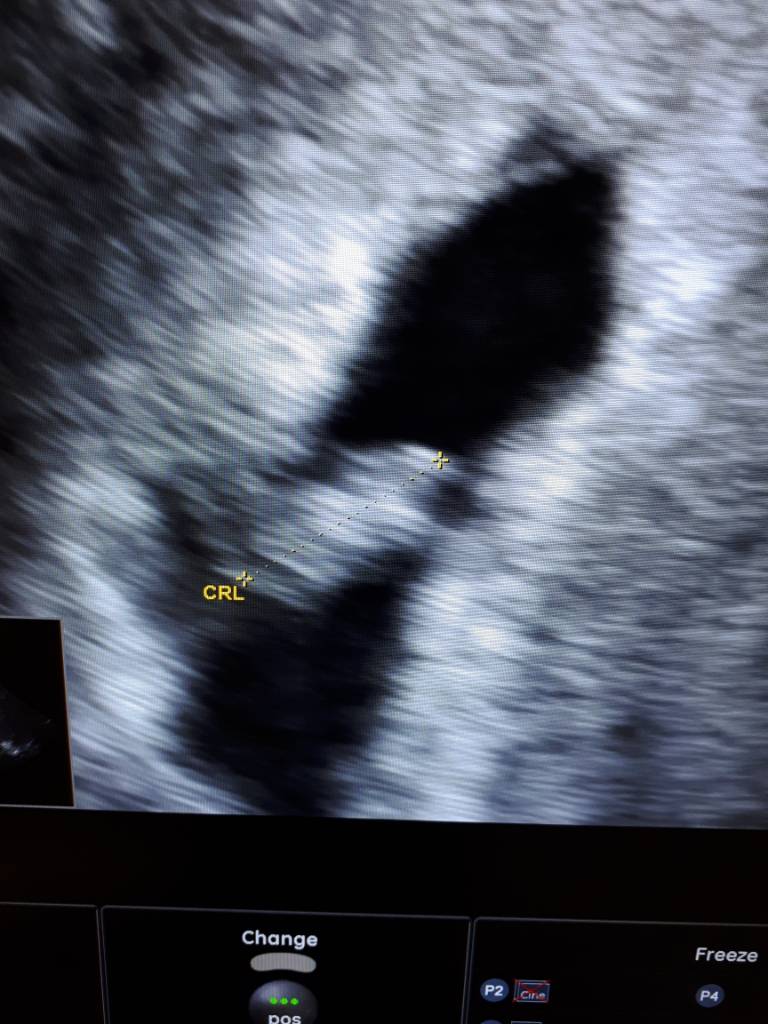

Hej dziewczynki! Dolaczam sie do Was z Warszawy. Ginka mowi zeby odliczac czas do 5 pazdziernika.. hehe. Dzis 7 i 2. Wlasnie wrocilam z wizyty. Tam podobno u mnie w brzuchu siedza BLIZNIAKIII!!! a dzis slyszalam dwa male serduszka :) jestem w szoku. Pewnie troche minie nim dojde do siebie.